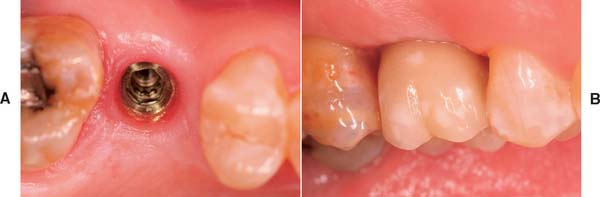

Several systems have been developed to comply with these demands. Common indications include congenitally missing maxillary lateral incisors (Fig. 13-42) and teeth in which endodontic treatment was unsuccessful (Fig. 13-43). Screw loosening has most commonly been associated with the terminally positioned single molar implant crown (Fig. 13-44).

Fig. 13-43 A, Occlusal view of a single tooth implant crown replacing a fractured mandibular premolar. B, Implant crown with screw access restored.